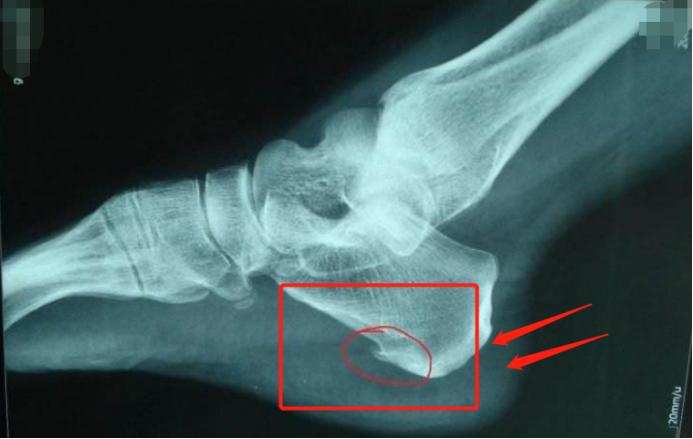

各位朋友可以先看一张图:

(可见红圈位置的骨头明显多了一根“小刺”)

这是一张典型的脚后跟骨赘图片,也就是许多老百姓说的“骨刺”、“骨质增生”。

像图片这种骨赘,就是许多人脚后跟痛的重要原因。